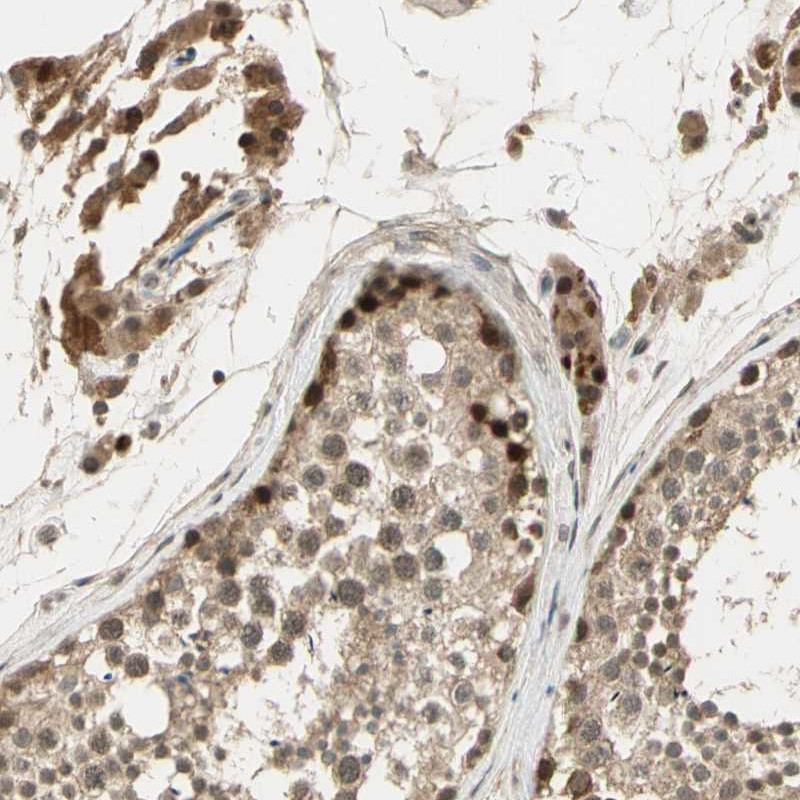

Immunohistochemical staining of human testis shows moderate nuclear positivity in cells in seminiferous ducts.